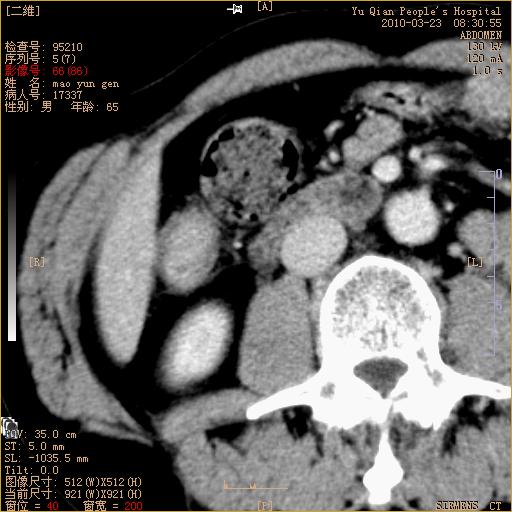

标题: CT25266:消瘦月余,前来肝部检查,请看看肠腔 [打印本页]

标题: CT25266:消瘦月余,前来肝部检查,请看看肠腔

肝区结肠占位,腺癌可考虑,建议肠镜活检。

升结肠肠壁增厚,不均强化,考虑升结肠腺癌可能性,建议肠镜检查。

1)考虑升结肠癌。2)右肾小囊肿。